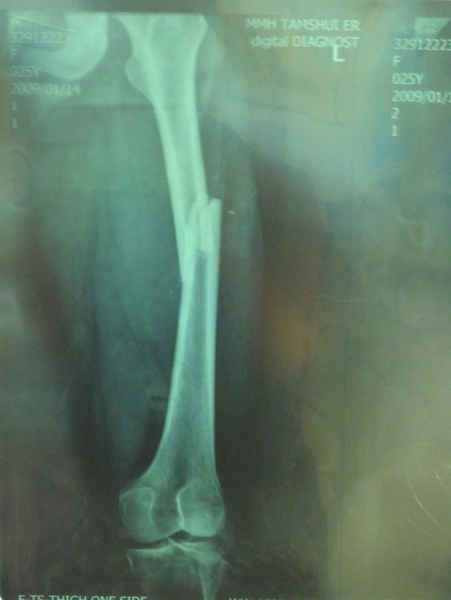

從去年2009/01/14 車禍大腿骨折後(見上圖)

腿裡就裝著鋼釘,也開啟了我半年拿拐杖的生活